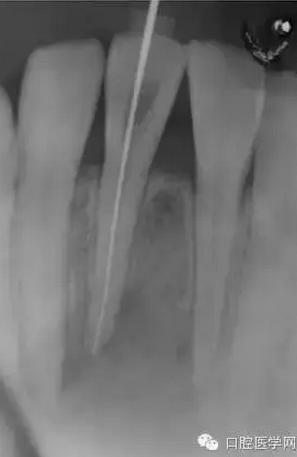

(圖 2) 根管長(zhǎng)度測(cè)定

事先告知患者因相應(yīng)牙齒根尖周病變太大,通過(guò)常規(guī)的根管治療可能無(wú)法治愈,此時(shí)可能需要進(jìn)行根尖切斷術(shù),而且鄰近牙齒也可能需要進(jìn)行根管治療。

診當(dāng)日進(jìn)行了開(kāi)髓,測(cè)量根管長(zhǎng)度及根管成形。開(kāi)髓時(shí)釋放出嚴(yán)重的惡臭,而且可以看到大量膿液通過(guò)根管流出來(lái)。當(dāng)日于唇側(cè)腫脹部位的最下端進(jìn)行了半月形切

口,使膿液從切口處流出,通過(guò)根管和切口,使用大量地生理鹽水清洗根尖病灶部位。當(dāng)天根管成形后,為防止食物塞入根管內(nèi),并便于膿液或氣體的排出,使用棉

球封住根管口。